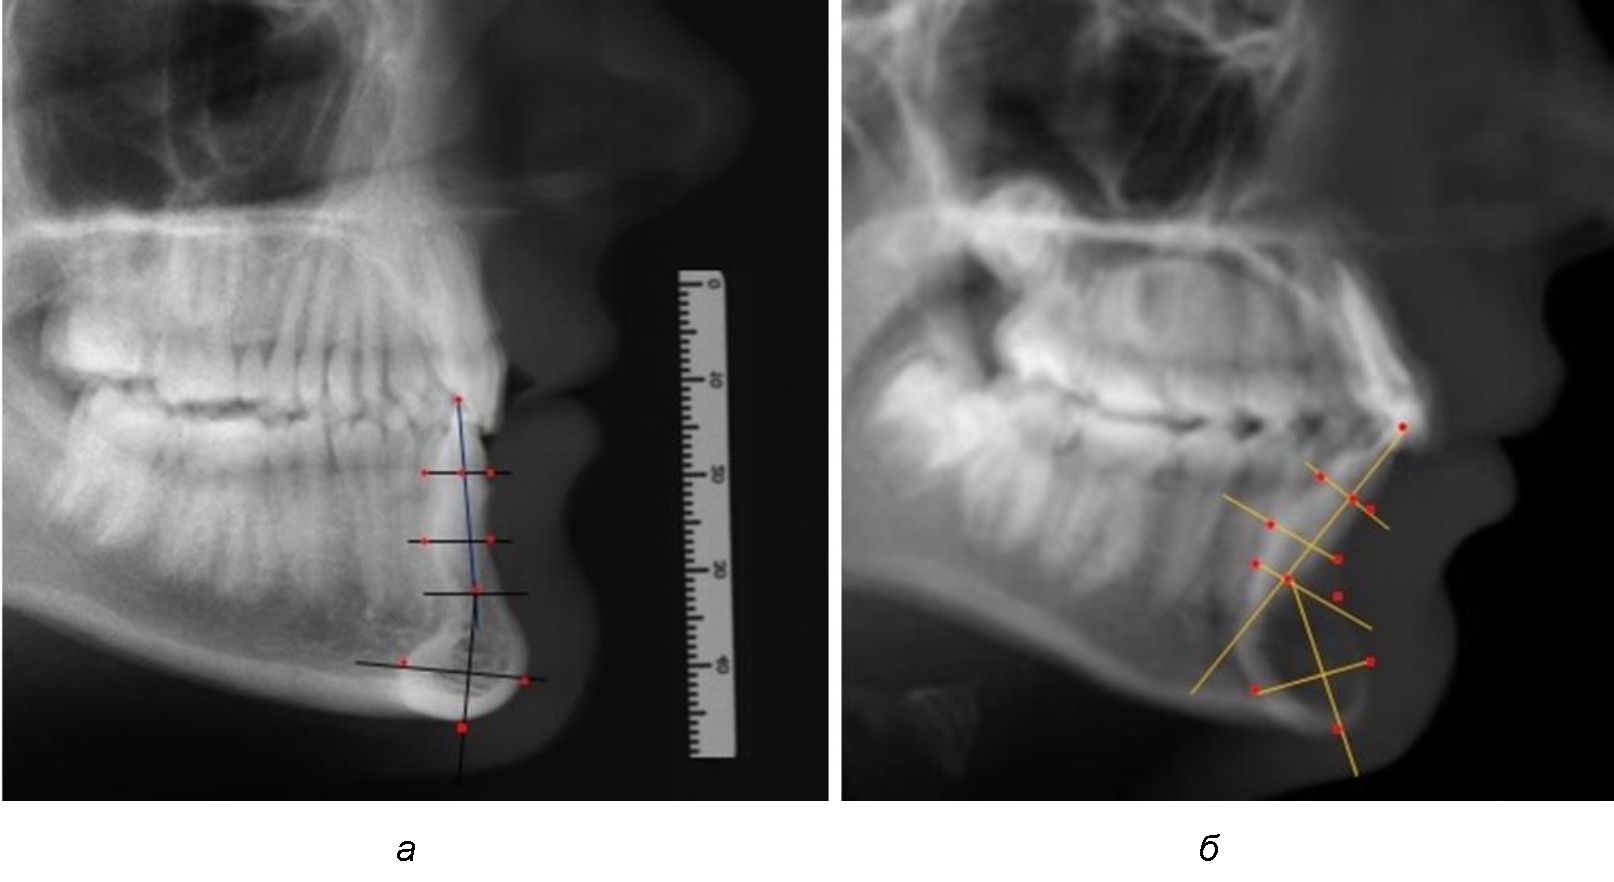

На режущем крае нижнечелюстного резцового сегмента устанавливалась точка, обозначаемая как IsL.

Определяли положение цервикальных точек резцов на вестибулярной и лингвальной поверхностях, которые соединяли цервикальной линией. Условная срединную вертикаль зуба соединяла резцовую точку IsL с серединой цервикальной линии и, как правило, доходила до апикальной точки, которую обозначали как Ap. Линия IsL–Ap определяла высоту зубоальвеолярной части резцового нижнечелюстного сегмента. Определяли высоту коронки и корня зуба. Кроме того, на вестибулярной поверхности зубочелюстного сегмента отмечали точку наибольшей вогнутости альвеолярной части, которая обозначалась как супраментальная точка Downs (Bsm). Измерялось расстояние IsL–Bsm, которое служило для определения проекции супраментальной точки Downs на язычную поверхность сегмента и обозначалась как точка Bsm'.

Проекцию верхушки корня резца на кость обозначалась как точка B нижнего апикального базиса по Schwarz. Соединяли апикальную точку с точкой нижнечелюстного апикального базиса линией, которая доходила до язычной поверхности подбородочного выступа и определяла положение точки B'. Таким образом, в зубоальвеолярной части сегмента выделялись две зоны: верхняя и нижняя, с последующим измерением по вертикали. При этом, как правило, верхняя зона была представлена компактной костной тканью, а в нижней зоне определялось наличие губчатой ткани между компактной пластинкой и стенкой альвеолы.

На нижнем контуре подбородочного выступа определяли положение ментальной точки Me. Линия, соединяющая апикальную точку с ментальной, определяла высоту подбородочного выступа тела нижней челюсти. Высота зубочелюстного сегмента IsL–Ме измерялась от резцовой до подбородочной точки. Вертикальная линия Ap–Me делила подбородочный выступ на две части: переднюю и заднюю (рис. 1).

Рис. 1. Ориентиры для исследования нативных препаратов (а) и рентгенограмм (б) резцового нижнечелюстного сегмента

Сагиттальные размеры зубоальвеолярной части сегмента определялись между точками Bsm и Bsm', в апикальной части сегмента – B и B'. В подбородочной части сегмента из передней выступающей точки подбородка Pog проводили линию перпендикулярно к линии Ар–Ме с определением точки Pog'. Расстояние Pog–Pog' определяло ширину подбородочного выступа.